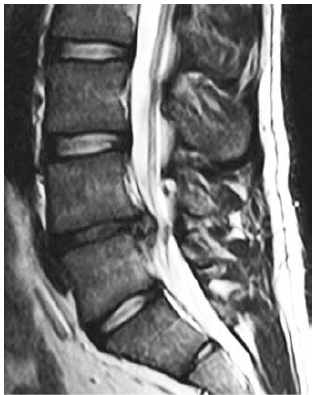

Observe a imagem a seguir.

Enunciado 2263454-1

Uma hérnia de disco lombar em segmento L4-L5 que ocorre em paciente jovem, com quadro agudo de forte ciática para MID, apresentando boa marcha após uso de AINES, mas paresia na extensão do hálux D e na dorsiflexão do pé, tem como melhor conduta: